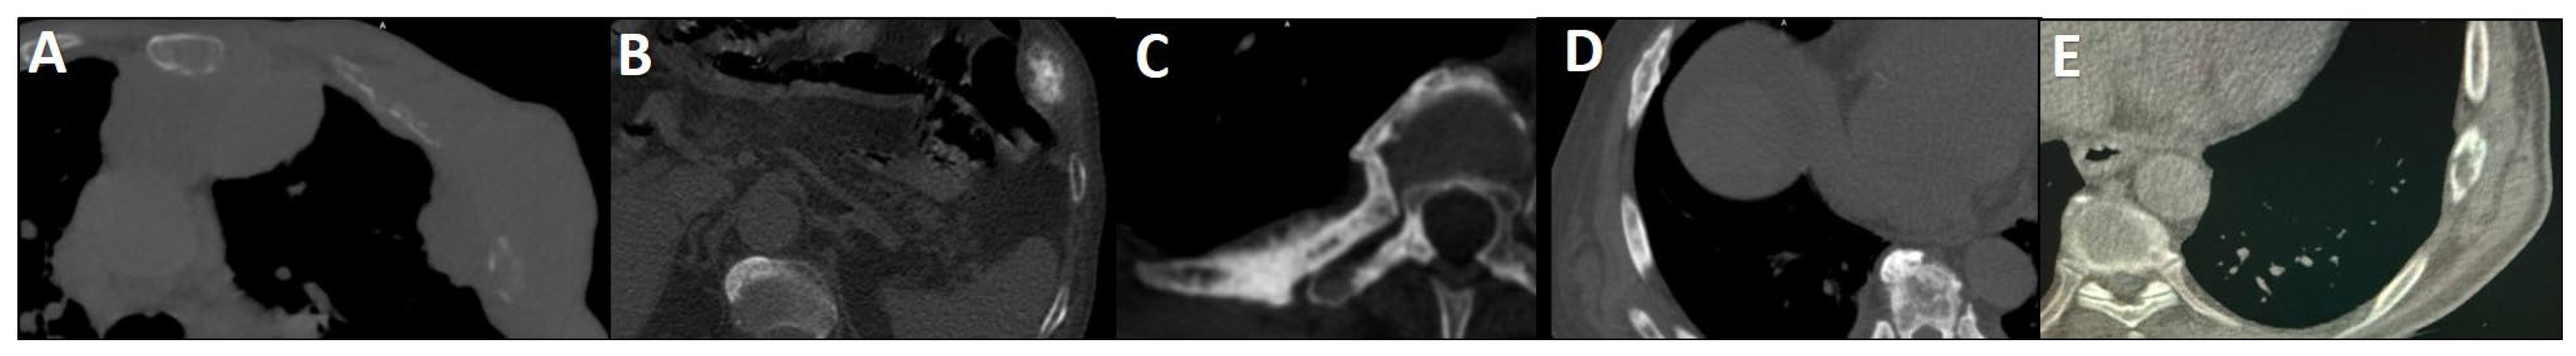

- Jochumsen, M.R.; Dias, A.H.; Bouchelouche, K. Benign traumatic rib fracture: A potential pitfall on 68Ga–prostate-specific membrane antigen PET/CT for prostate cancer. Clin. Nucl. Med. 2018, 43, 38–40. [Google Scholar] [CrossRef]

- Panagiotidis, E.; Paschali, A.; Giannoula, E.; Chatzipavlidou, V. Rib fractures mimicking bone metastases in 18F-PSMA-1007 PET/CT for prostate cancer. Clin. Nucl. Med. 2019, 44, e46–e48. [Google Scholar] [CrossRef]